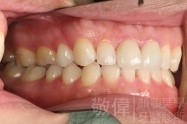

變臉矯正,原來戽斗妹跟大歪臉變成自信正妹

經由本院3D數影X光影像儀分析、與3D齒顎顏矯正技術,再配合口腔顎面正顎專科醫師施以正顎手術治療,雙方共同合作,使患者臉部外觀有很好的改善,大歪變小歪,產生了天南地北的大改變,她的人生也整個變得不一樣。

因為矯正與正顎手術的配合,使「戽斗妹」變成了「陽光正妹」,完全的改變了她的人生,在面對各種場合、與人交際都散發出自信微笑。所以,奉勸家長,如果小朋友有臉顎畸型的問題,應該考慮配合做這種簡單、安全、有效的正顎手術。